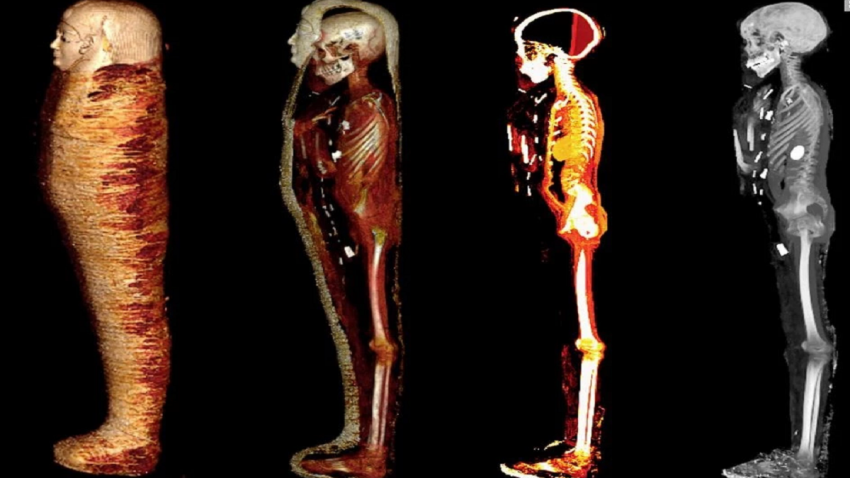

Madrid. Tomografías computarizadas permitieron “desenvolver digitalmente” a la momia intacta de aproximadamente 2 mil 300 años de antigüedad de un adolescente egipcio de alto nivel socioeconómico.

En este caso, científicos egipcios utilizaron la tomografía computerizada (TC) para “desenvolver digitalmente” a la momia intacta y nunca abierta de un adolescente de 2 mil 300 años de antigüedad y de alto nivel socioeconómico.

Descubrieron que este “chico de oro” es un escaparate intacto de las antiguas creencias egipcias sobre la vida después de la muerte. Por ejemplo, fue enviado con no menos de 49 amuletos de 21 tipos para promover su resurrección corporal. Llevaba sandalias y guirnaldas de helechos, ricas en significado ritual.

“Aquí mostramos que el cuerpo de esta momia estaba ampliamente decorado con 49 amuletos, bellamente estilizados en una disposición única de tres columnas entre los pliegues de las envolturas y dentro de la cavidad corporal de la momia –explica en Frontiers la doctora Sahar Saleem, primera autora del estudio y profesora de la Facultad de Medicina de la Universidad de El Cairo (Egipto). Entre ellos figuran el ojo de Horus, el escarabajo, el amuleto akhet del horizonte, la placenta, el nudo de Isis y otros. Muchos eran de oro, otros de piedras semipreciosas, arcilla cocida o loza y su finalidad era proteger el cuerpo y darle vitalidad en la otra vida.”

La momia estaba depositada dentro de dos ataúdes, uno exterior con una inscripción griega y otro interior de madera. Dentro llevaba una máscara dorada para la cabeza, un cartonaje pectoral que cubría la parte delantera del torso y un par de sandalias. Aparte del corazón, las vísceras habían sido extraídas mediante una incisión, mientras el cerebro había sido sacado por la nariz y sustituido por resina.

Los escáneres mostraron que el niño medía 128 centímetros, no estaba circuncidado y no se le conocía otra causa de muerte que la natural. Por el grado de fusión ósea y la ausencia de erupción de las muelas del juicio, los autores estiman que el niño tenía entre 14 y 15 años. Sus dientes estaban en buen estado, sin evidencia de caries, pérdida de piezas o enfermedad periodontal.

Un nudo de Isis invocaba el poder de ésta para proteger el cuerpo, un amuleto de ángulo recto aportaba equilibrio y nivelación, y los penachos dobles de halcón y avestruz representaban la dualidad de la vida espiritual y material. En el interior de la cavidad torácica se encontró un escarabajo dorado, del que los investigadores imprimieron una copia en 3D.

A la vista de estos resultados, la dirección del Museo Egipcio decidió trasladar a la momia a la sala principal de exposiciones con el sobrenombre de Niño de oro. En su nueva ubicación, los visitantes pueden admirar sus imágenes de TAC y una versión impresa en 3D del amuleto del escarabajo del corazón, para acercarse lo más posible a las glorias de la antigua civilización egipcia.